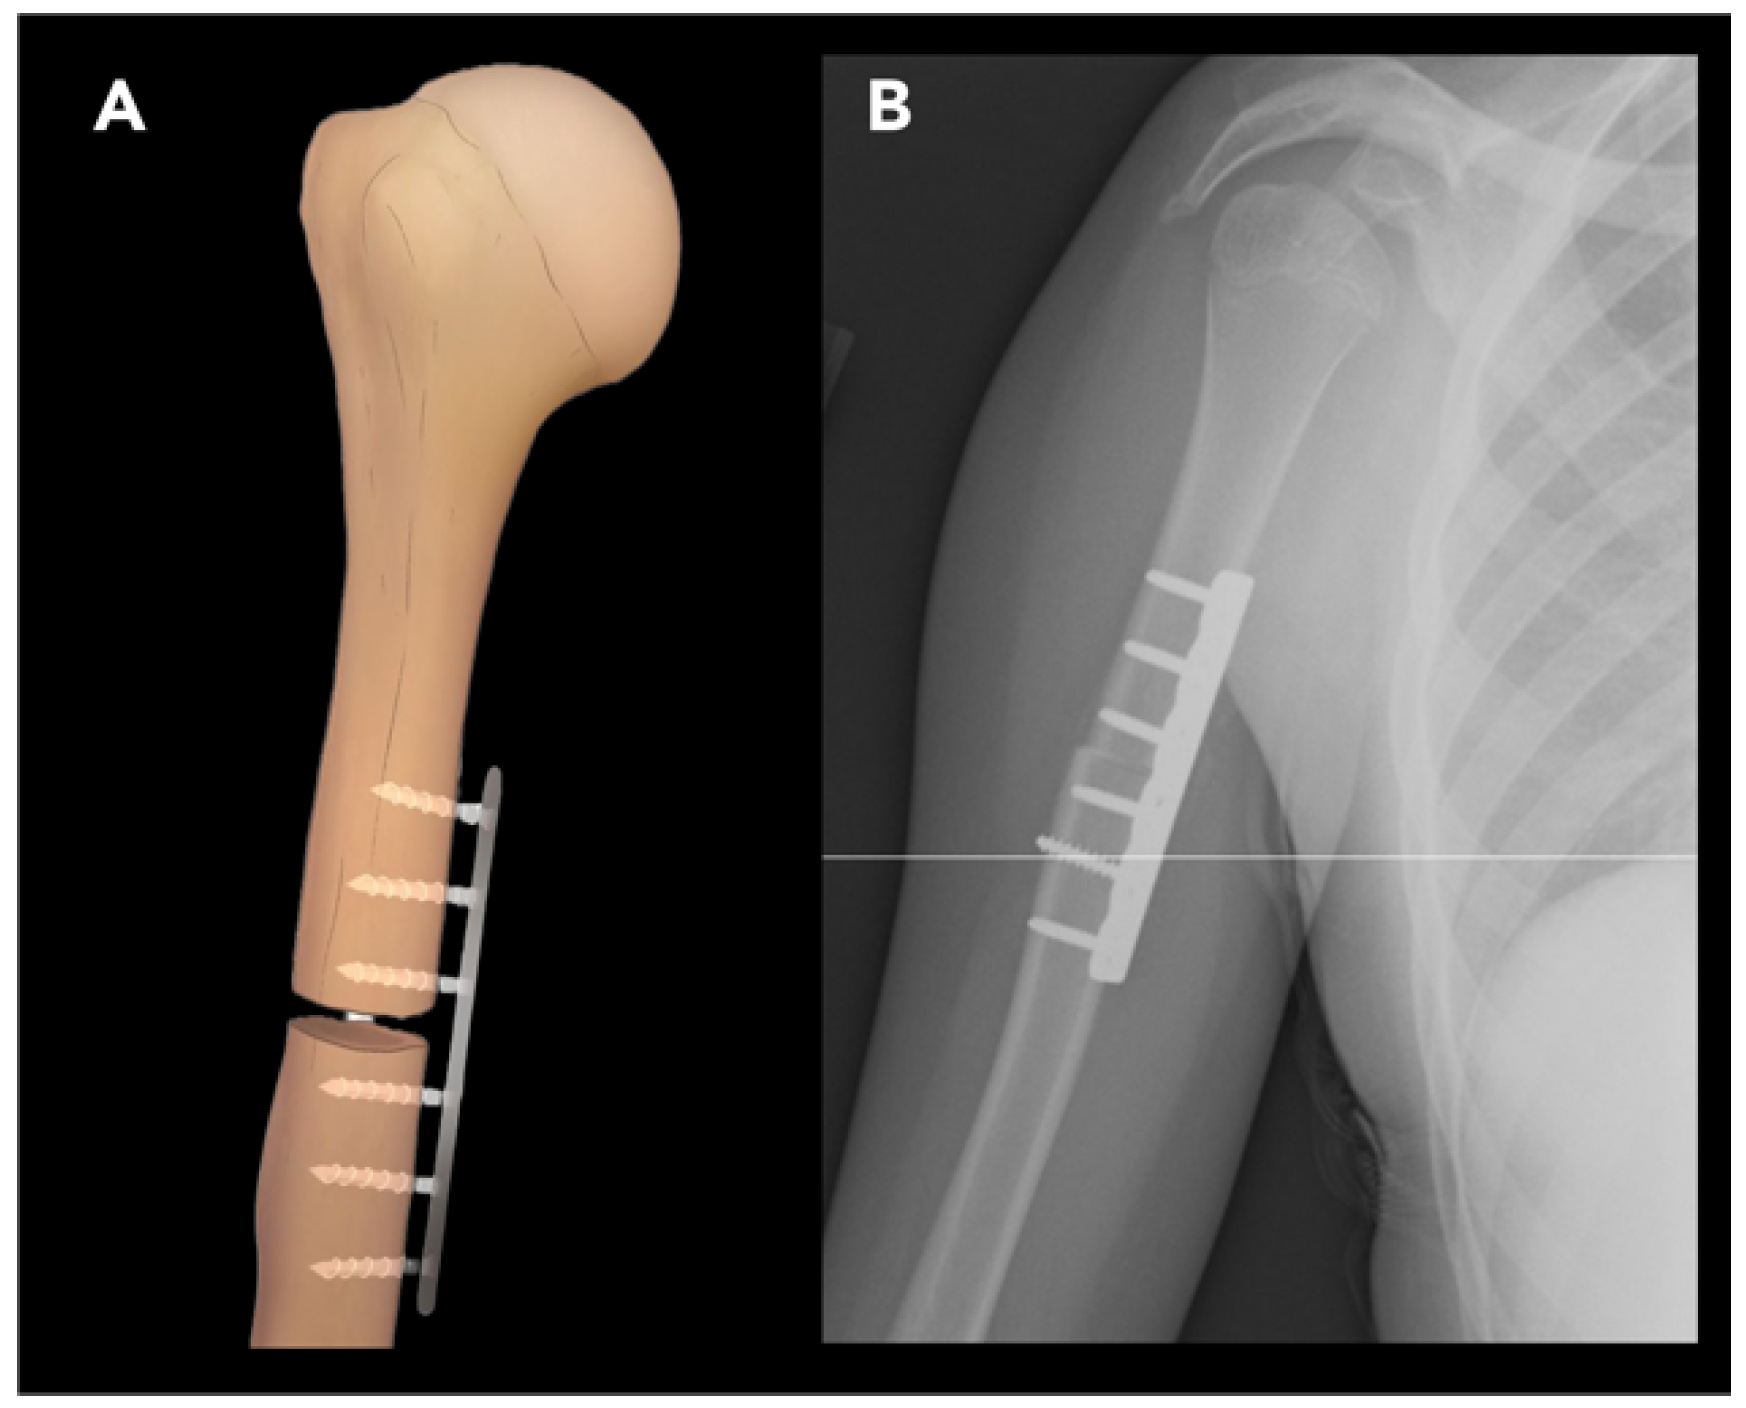

2.2.1. External Rotation Humeral Osteotomy